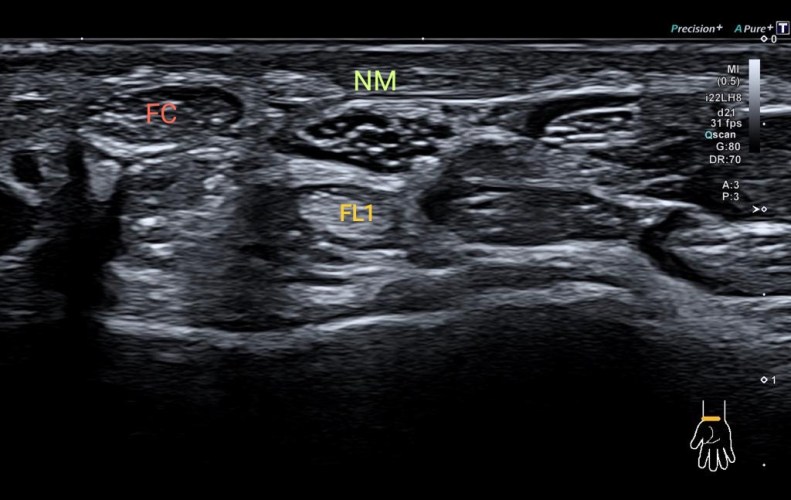

4. Muñeca región Flexora. Anatomía vista con una sonda Stick Hockey de 22Mhz en un equipo Canon Medical Systems Europe i800.

Observa el entramado del Nervio Mediano a su paso por la Muñeca con una semiología en panal de abeja típico de un nervio periférico normal. Lo acompañan flexor del primer dedo (F1) y flexor del carpo (FC) en el corte en eje corto.